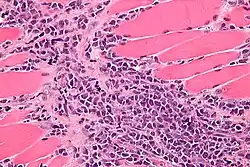

| Micrograph of a myeloid sarcoma within muscle. H&E stain. | |

A myeloid sarcoma (chloroma, granulocytic sarcoma,[1]: 744 extramedullary myeloid tumor) is a solid tumor composed of immature white blood cells[2] called myeloblasts. A chloroma is an extramedullary manifestation of acute myeloid leukemia; in other words, it is a solid collection of leukemic cells occurring outside of the bone marrow.